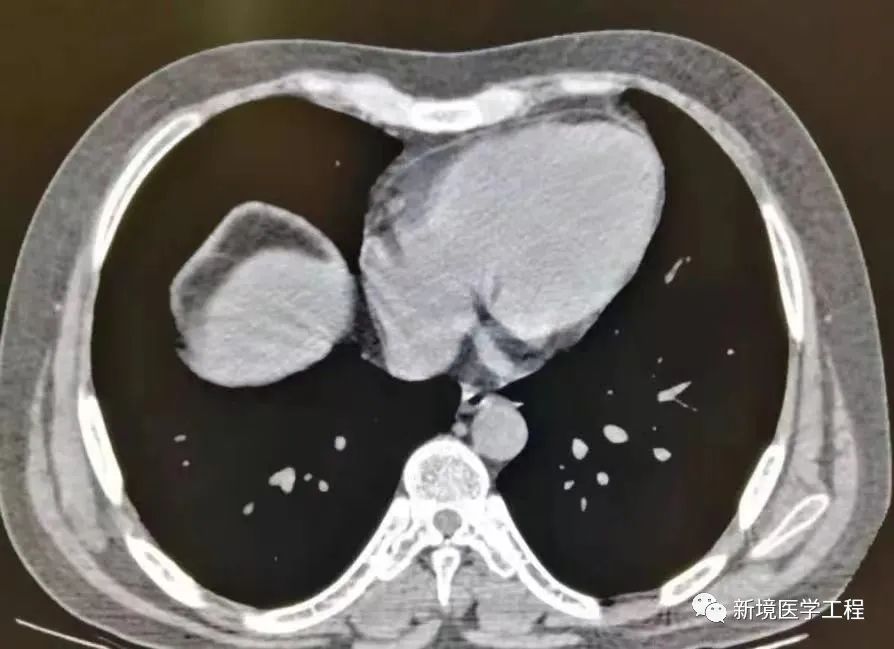

各种成像模式的原理和伪像发生的机制

伪像常见的表现机制;